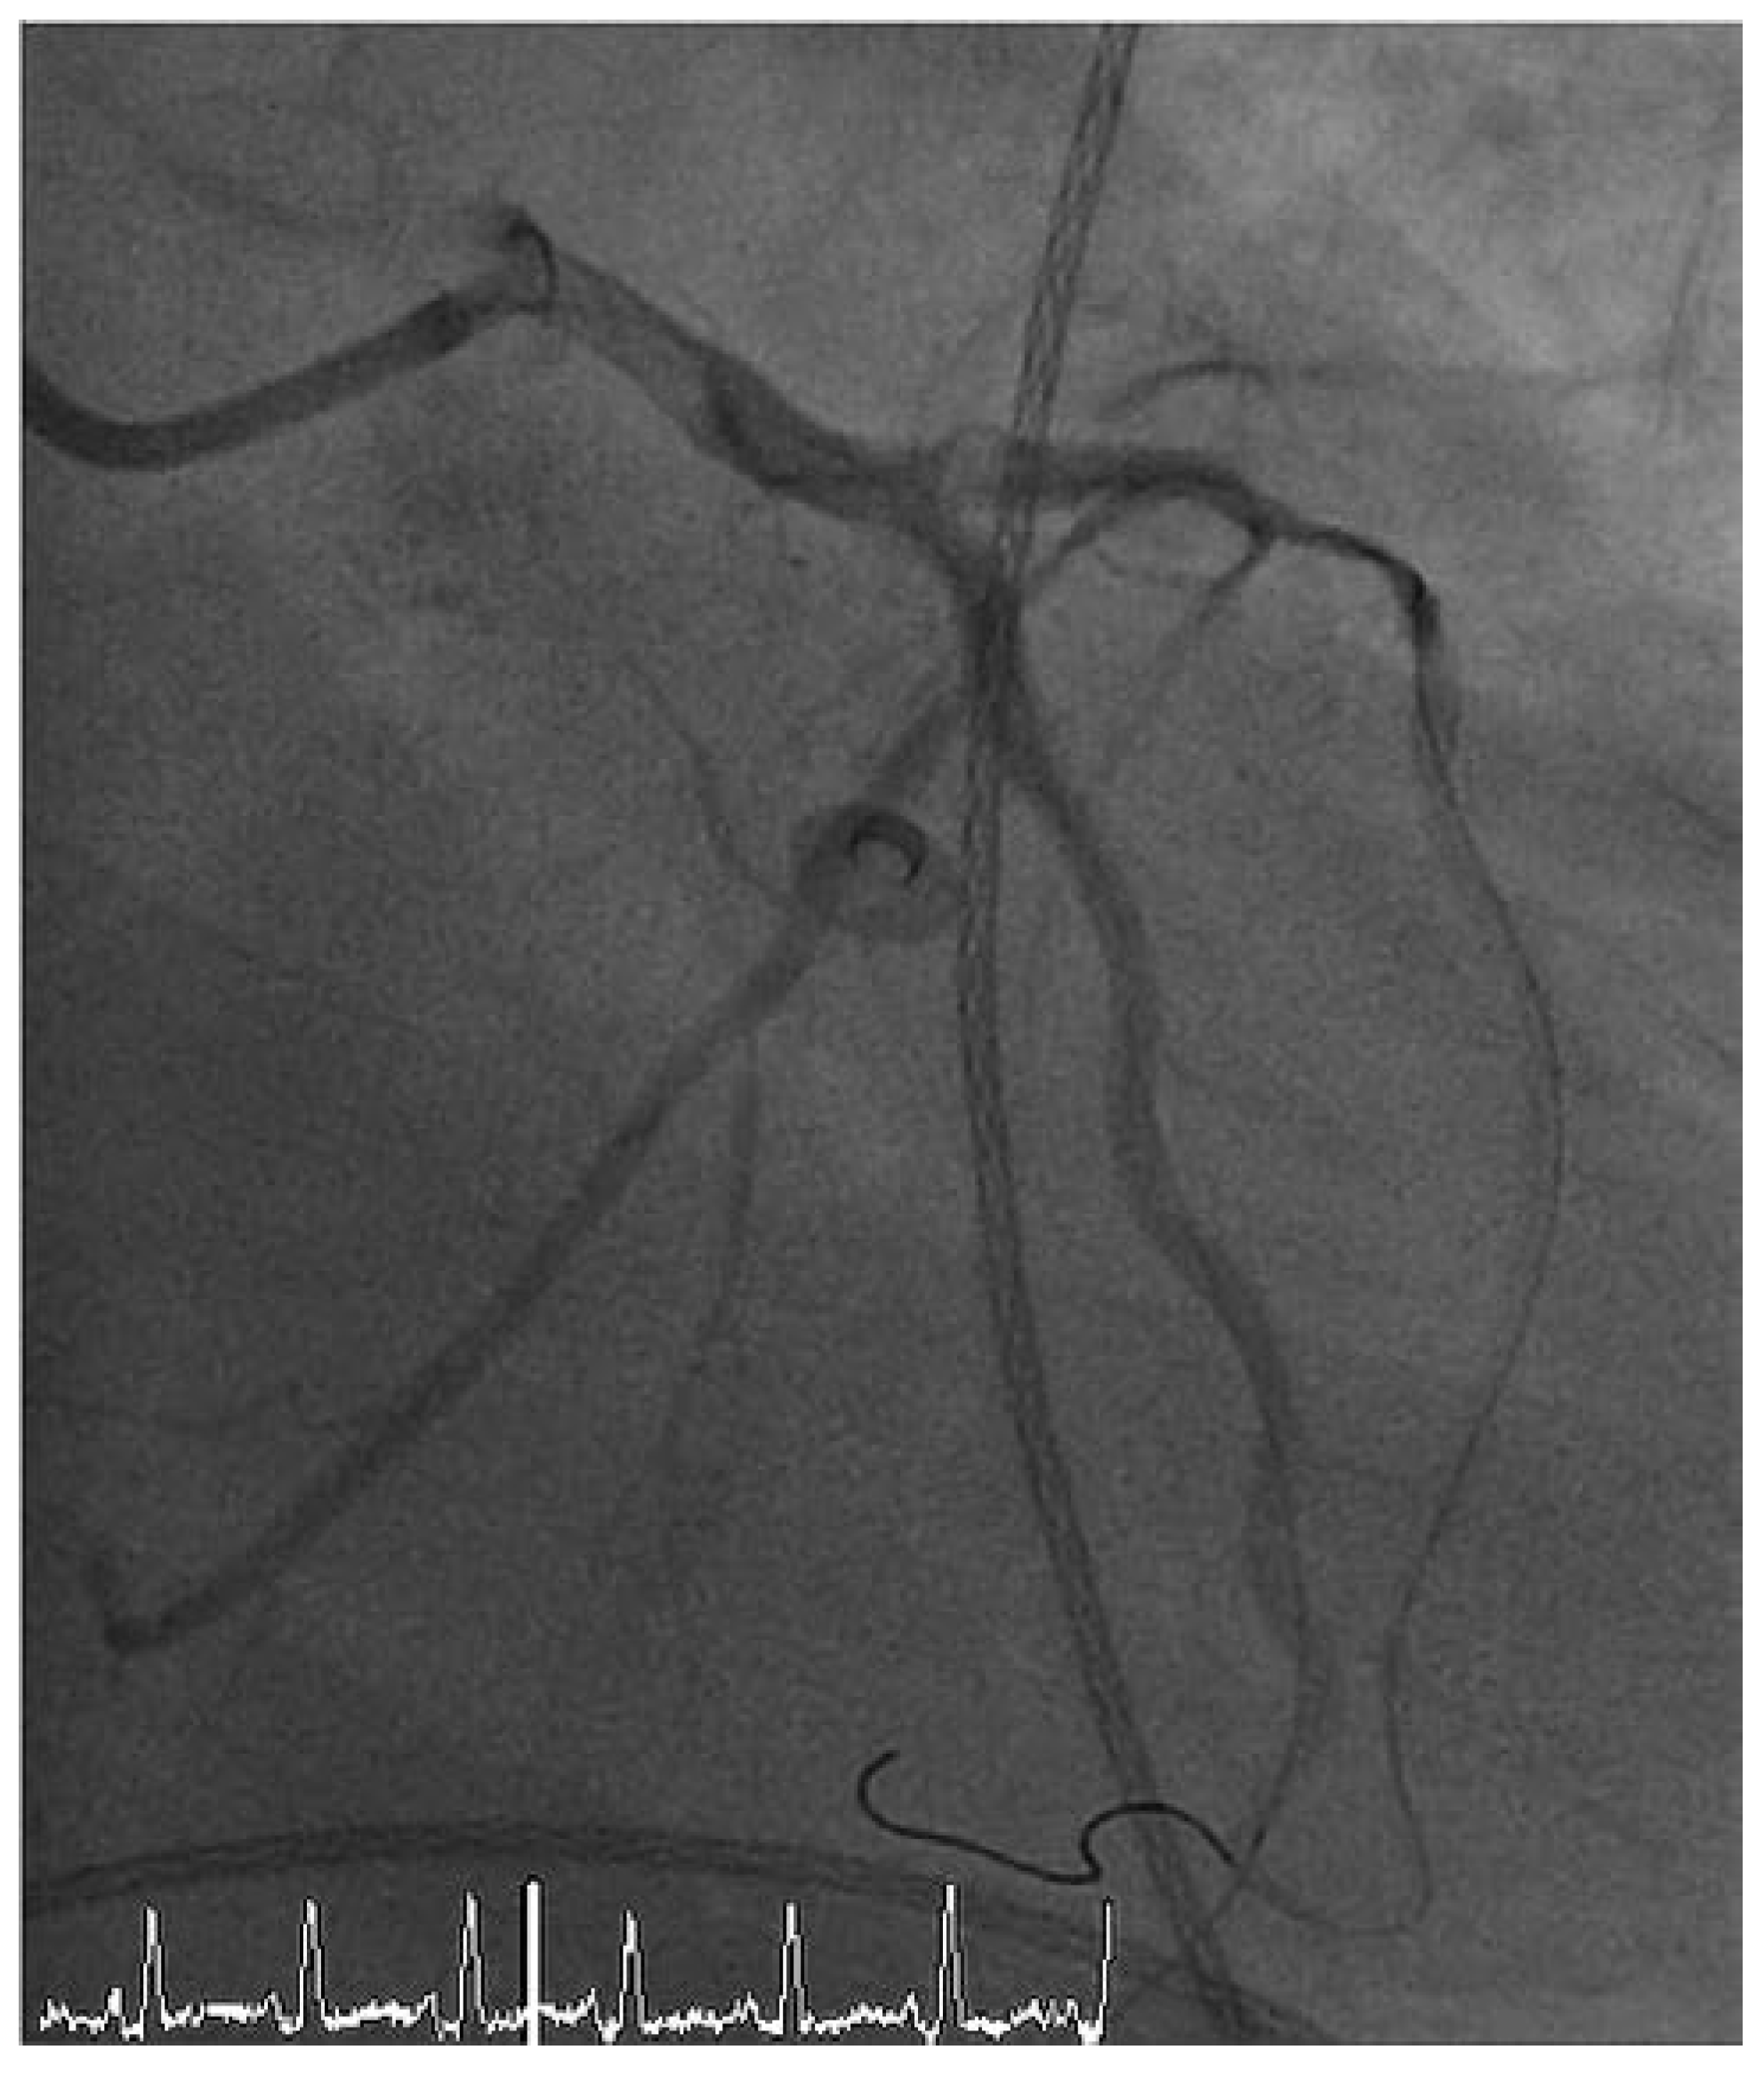

Unter diesem hämodynamischen Backup gelang die Durchführung der PCI mit Rekanalisation des RIVA mittels PTCA und 3-fach-Stent-Implantation (3× «drug eluting» Stents [DES]) sowie die Wiedereröffnung der subtotalen Stenose des Intermediärastes (PTCA/1× DES). Zudem konnte die hochgradige Hauptstammstenose mittels primärer Stentimplantation (1× DES) versorgt werden. Die Kontrollangiographie dokumentierte ein gutes postinterventionelles Ergebnis mit promptem Fluss bis in die Peripherie (Thrombolysis in myocardial Infarction-Klassifikation [TIMI] III) (Abbildung 2). Der Verschluss des arteriellen inguinalen Zugangs erfolgte mittels eines herkömmlichen perkutanen Verschluss-Systems (Angio-SealTM, St. Jude Medical, MN, USA).

Abbildung 2. Koronarangiographie nach Intervention – Fall 1.